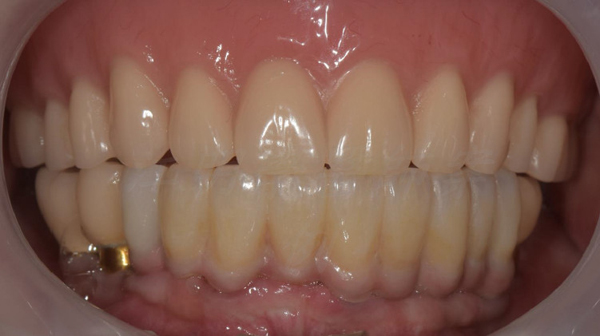

治療後

這些照片展示了您的牙齒在術後得到顯著改善,更加整齊、美觀,並達到理想的咬合狀態。